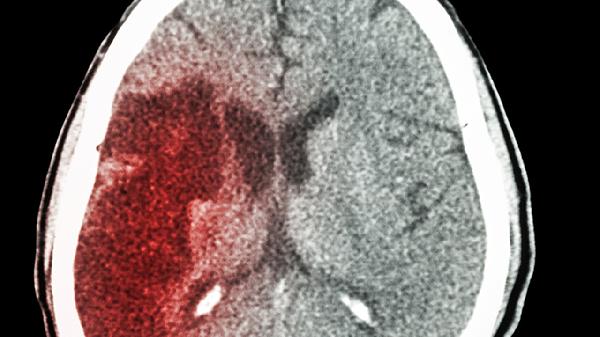

47岁脑出血导致偏瘫还能活多久

47岁发生脑出血导致偏瘫的患者,通常有5年以上的生存期,但具体时长会受到出血位置、并发症控制情况、康复治疗效果、基础疾病管理以及家庭护理水平等多个因素的影响。

如果出血发生在基底节区,患者的存活几率相对较高;而如果出血在脑干或者范围较大,预后则较差。如果关键区域受损,可能会对生命体征造成直接影响;但如果是在非功能区,通过系统的康复训练,还是有可能恢复部分功能。